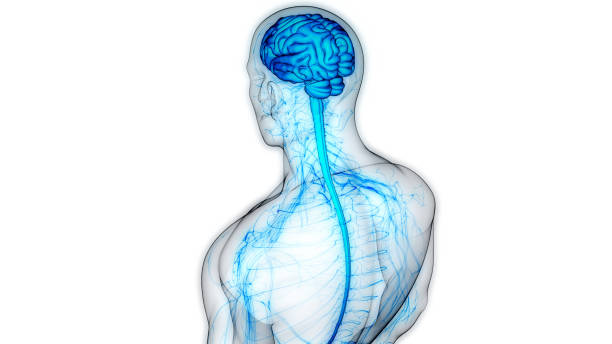

✅척추전방전위란?

척추는 원래 바로 떨어져 있어야 합니다. 하지만 전방 전위는 척추가 앞으로 치우쳐져 있는 상태를 말합니다. 이는 크게 두 가지 원인으로 나눌 수 있습니다.